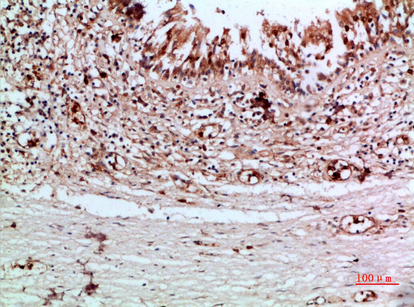

Immunohistochemical analysis of paraffin-embedded human-thyroid, antibody was diluted at 1:200